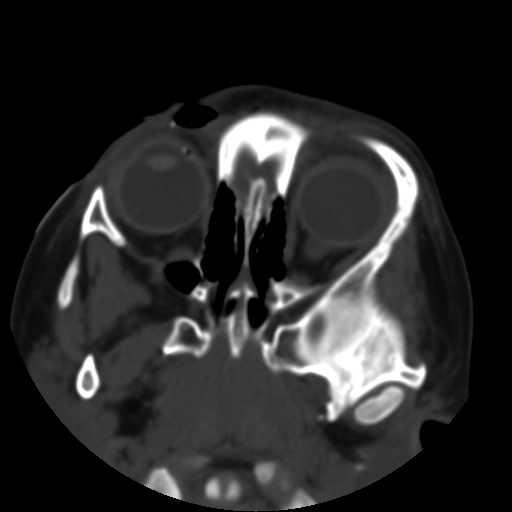

以下是引用深泽交通医院在2009-10-16 8:25:00的发言:[br]右眼环出血伴异物

以下是引用卜一在2009-10-16 15:01:00的发言:[br]右眼球挫裂伤伴异物!

以下是引用拾荒者在2009-10-17 18:38:00的发言:[br]鼻面部皮下积气,右侧睑缘及眼球壁高密度异物影,左侧眼球壁晶状体内侧缘处是圆形低密度影。低密度异物?应提请眼科医生注意。